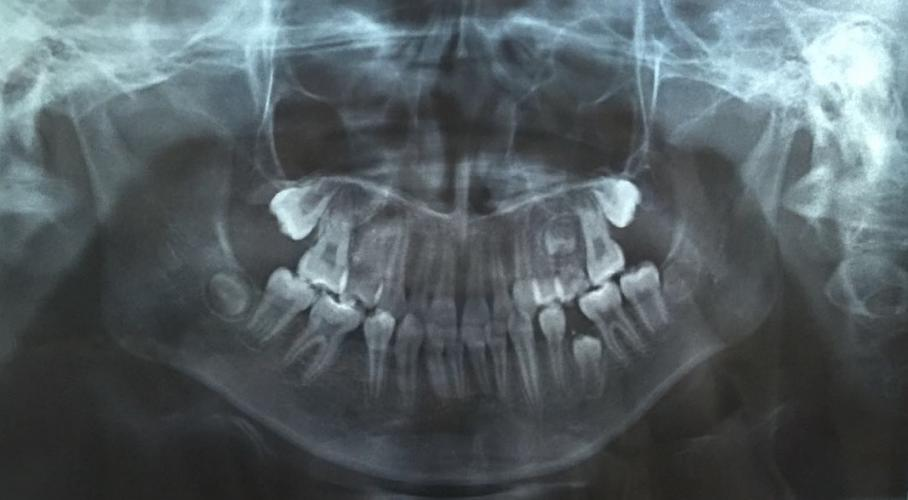

圖片由院方提供

兒童口腔科副主任醫(yī)師王銳副教授為琦琦拍攝了一張曲面斷層片,發(fā)現(xiàn)琦琦左下后牙區(qū)有一顆牙齒因間隙不足阻生,建議家長接受矯正調(diào)節(jié),擴(kuò)開間隙,觀察阻生于頜骨內(nèi)的牙齒是否可以順利萌出。調(diào)節(jié)過程相對復(fù)雜,調(diào)節(jié)周期較長,需要每隔一個(gè)月復(fù)診一次?!昂⒆咏衲晟铣踔?,課業(yè)壓力越來越大,但既然牙齒出現(xiàn)這么嚴(yán)重的問題,擠時(shí)間也要積極配合醫(yī)生調(diào)節(jié)。”面對這種情況,琦琦媽媽無奈的說。

據(jù)王銳副教授介紹,孩子的乳牙脫落要及時(shí)到醫(yī)院拍攝曲面斷層片觀察是否存在乳牙早失、恒牙阻生或發(fā)育異常等情況,一旦發(fā)現(xiàn)乳牙早失必須及時(shí)制作間隙保持器保留牙齒間隙,給恒牙足夠的萌出空間,避免嚴(yán)重后果。